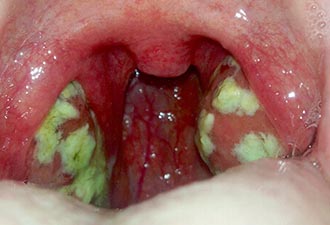

- тонзиллит;

Фарингит — это воспаление слизистой оболочки глотки, тонзиллит — воспаление миндалин, а ларингит — поражение слизистой гортани. Обычно эти заболевания имеют острое инфекционное происхождение, вызванное респираторными вирусами (например, аденовирусами, респираторно-синцитиальным вирусом) или бактериями (такими как стафилококки и стрептококки). Если воспаление затрагивает несколько областей одновременно, пациенты могут ощущать симптомы, характерные для всех этих отделов. Чаще всего, помимо боли, присутствуют сухость и першение в горле. Важно отметить, что боль ощущается «внутри горла», а внешние изменения на шее отсутствуют.

Если боль сопровождается осиплостью голоса (ларингит), необходимо соблюдать режим молчания (голосовой покой) в течение нескольких дней и проводить ингаляции с лекарственными препаратами. При сильной боли можно использовать местные анестетики и анальгетики в форме спреев или леденцов (например, Тантум Верде или Стрепсилс Интенсив). В случае ОРВИ обычно достаточно этих мер, однако при бактериальном тонзиллите (особенно стрептококковом) потребуется назначение антибактериальных средств.